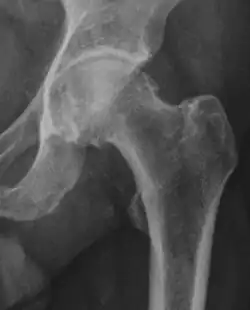

Projectional radiography ("X-ray") is often considered first line for FAI.[10] Anterior-posterior pelvis and a lateral image of the hip in question should be attained.[10] A 45-degree Dunn view is also recommended.[10][19]

| Alpha angle | ![]() |

Degree of bulging of the femoral head-neck junction: In normal conditions there is a symmetric concave contour at the junction of the femoral head and neck. Loss of this concavity or bone bulging may lead to cam type impingement. The degree of this deformity can be measured by the alpha angle. Although it can be measured in the cross-lateral view, the 45° Dunn view is considered more sensitive and the frog leg view more specific in determining pathologic values. |

|